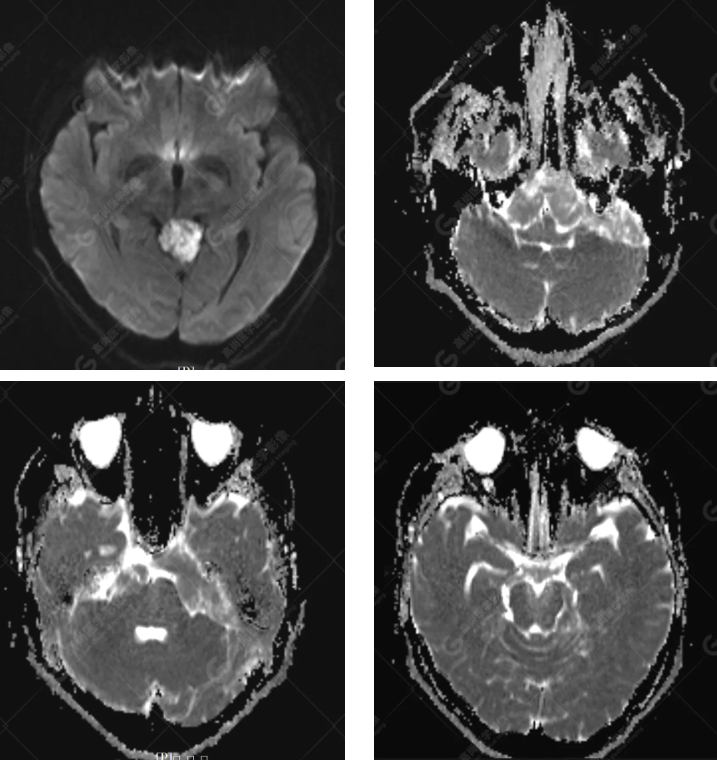

MRI 影像所见:

延髓池、桥前池、双侧桥小脑角区、鞍上池至左侧小脑幕下见团片状异常信号影,呈长 T1 长 T2 信号,FLAIR 序列呈不均匀稍低信号,DWI 序列呈高信号,ADC 图低信号,增强后无强化。右侧面听神经受压向后移位,双侧三叉神经及左侧面听神经被包埋,显示不清。

延髓池、桥前池、双侧桥小脑角区、鞍上池至左侧小脑幕下胆脂瘤,右侧面听神经受压向后移位,双侧三叉神经及左侧面听神经被包埋

MRI 表现为 T1WI 呈略高于脑脊液的低信号,T2WI 呈均匀高信号,信号接近于脑脊液,T2-FLAIR 序列上病灶信号未完全被抑制高于脑脊液,DWI 高信号,ADC 低信号(具一定特征性)。